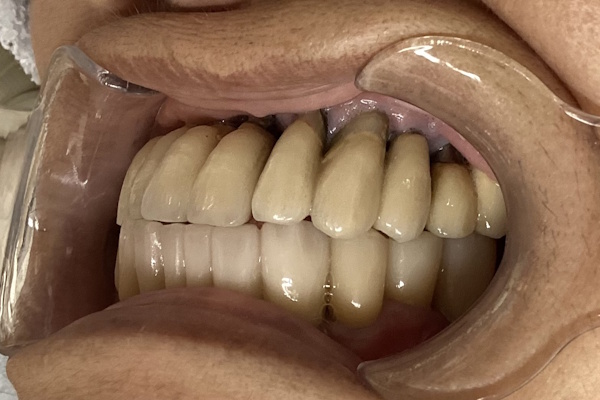

実際の見た目の写真

「下の入れ歯が合わない」ということでご来院いただきました。インプラント治療で快適に噛めるようになりました。